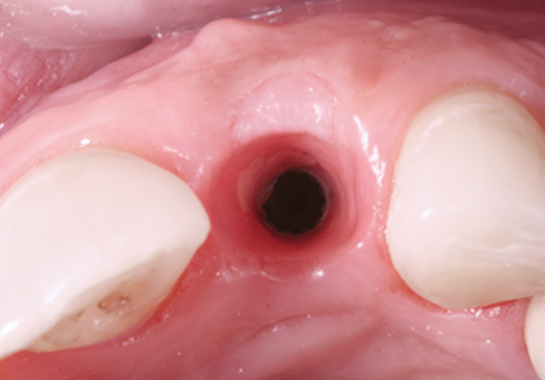

L’intervention elle-même débute par une incision précise de la gencive pour accéder à l’os sous-jacent. Le site receveur est soigneusement préparé pour accueillir le matériau de greffe. Celui-ci est alors mis en place avec précision, parfois accompagné de membranes de régénération pour guider la croissance osseuse. L’intervention se termine par la suture méticuleuse de la gencive.

La période de suivi et de cicatrisation

Enfin, le suivi et la cicatrision s’étendent sur plusieurs mois. Des rendez-vous de contrôle réguliers permettent au chirurgien de surveiller la progression de la cicatrisation. La durée moyenne de cicatrisation avant la pose d’implants varie généralement de 4 à 6 mois, selon le type de greffe et la réponse individuelle du patient.